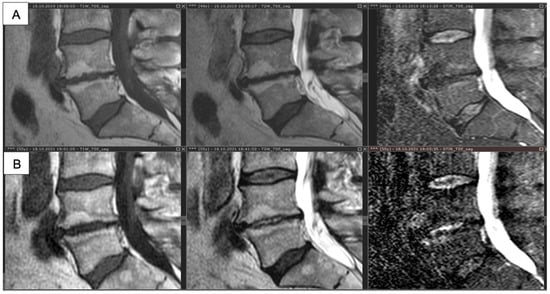

- Borshchenko, I.; Sobol, E.; Shekhter, A.; Baskov, A.; Grin, A.; Borshchenko, M. Biological non-ablative repair of lumbar discs by transforaminal intradiscal laser irradiation: MRI quantitative analysis of the effects—Preliminary report. Lasers Med. Sci. 2020, 11. [Google Scholar] [CrossRef]